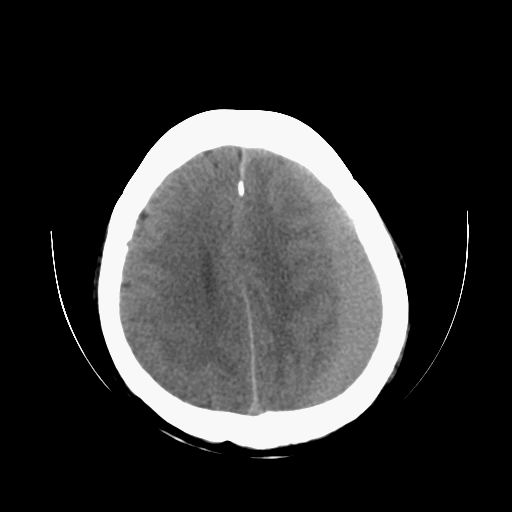

标题: CT13217:头部外伤三月余,头痛三天 [打印本页]

标题: CT13217:头部外伤三月余,头痛三天

左侧慢性硬膜下血肿

太典型,左侧慢性硬膜下血肿

左侧慢性硬膜下血肿,大脑镰下疝。

支持左额颞顶慢性硬膜下血肿伴大脑镰下疝。

血肿是急性、亚急性、还是慢性,要结合外伤时间考虑的,本例头部外伤三个月,应该是明显的慢性硬膜下血肿,但血肿的等密度显然不符合病理改变,估计是合并再次出血,中线结构移位明显,有脑疝形成。应穿刺减压。

血肿是急性、亚急性、还是慢性,要结合外伤时间考虑的,本例头部外伤三个月,应该是明显的慢性硬膜下血肿,但血肿的等密度显然不符合病理改变,估计是合并再次出血,中线结构移位明显,有脑疝形成。应穿刺减压。 大于2个月为慢性出血,2周到二个月为亚急性出血